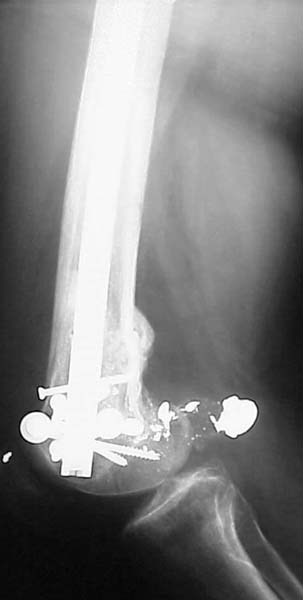

Yesterday antegrade closed nailing was performed (UFN 10 mm). Two cancellows screws added to fix the lateral condyle. The surgery was not too easy, and extension of condylar part i failed to reduce completely. The shaft looks even more ugly. The patient left for a couple of days in 90/90 position. Comments/opinions/advices are welcome.

Since it was done closed the shaft will heal or at worst need an exchange IMN.

Congratulations! Tough case. I think you achieved the best achievable result which possible with this method for this complex injury.

See attached case that was done several years ago before LISS. He had comminuted trochlea and anterior blocking screws were used to prevent anterior IMN cut-out.